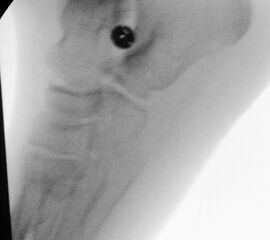

=> Kleinkindalter mit knorpeligen Knochenanlagen

Minimalinvasive Techniken in der Fußchirurgie werden mit unterschiedlichen Fräsen in unterschiedlichen Größen, angepasst an das Knochenformat, durchgeführt. Kindliche Knochen ossifizieren erst mit zunehmendem Wachstum. Im Alter von sieben Jahren verknöchert zuletzt das Os navikulare. Knorpelige Anlagen können nicht mit einer Fräse osteotomiert werden (Abb. 9). Daher sollte die minimalinvasive Fußchirurgie (MIS) ca. ab dem 8. Lebensjahr durchgeführt werden.

Abb. 9: Röntgenbild mit noch ausgeprägten Knorpelanlagen mit geringer Verknöcherung.